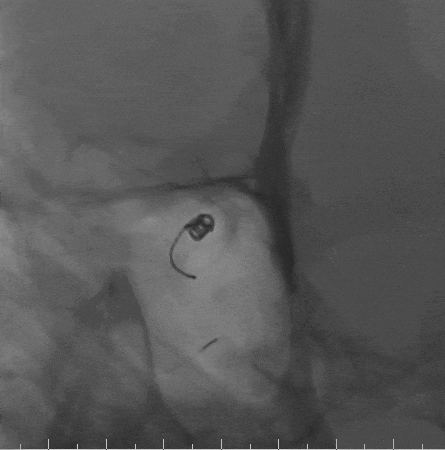

术前影像

栓塞过程

Tethys®中间导引导管到达C2段远端,上行第一根栓塞微导管,至动脉瘤瘤颈口,并填入一枚Jasper®SS弹簧圈;上行第二根栓塞微导管至动脉瘤子囊,并填入一枚Jasper®SS弹簧圈,再填入多枚Jasper®SS弹簧圈。